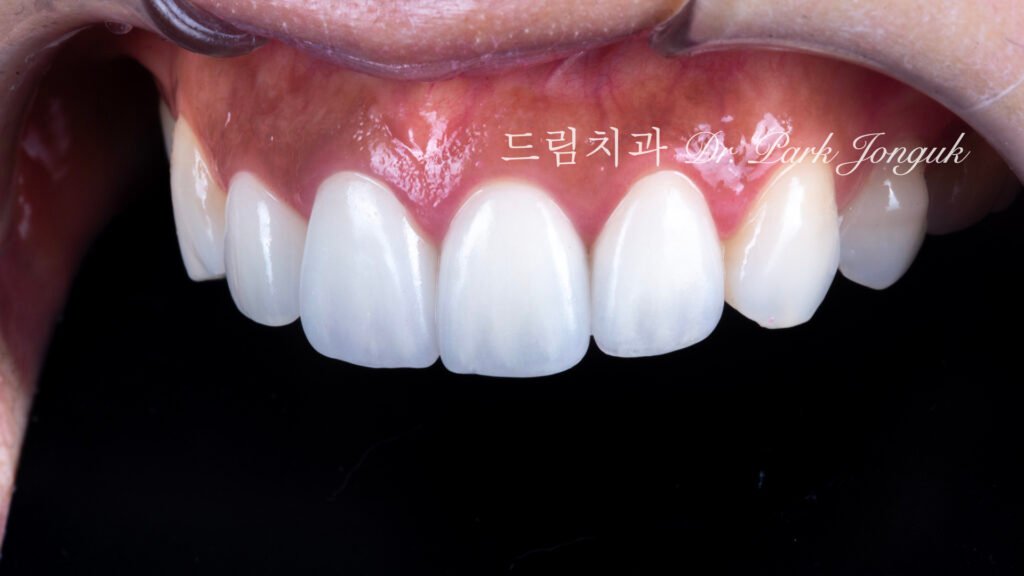

최종 결과: 4년 추적 관찰의 성공

사진 4, 5, 6은 치료 후 4년이 경과한 상태입니다. 놀라운 장기 안정성을 보여줍니다.

투명감과 자연스러움

투명감이 살아 있으면서도 자연스럽고 밝은 치아가 되었습니다.

절단연 투명감(Incisal translucency): 치아 끝의 투명감이 아름답게 표현되어 빛이 부드럽게 투과하고 산란(Light scattering)됩니다.

젊고 건강한 인상: 투명감은 젊고 건강한 치아의 특징으로, 노화되거나 병적인 치아는 불투명합니다.

색상 회복

밝고 생동감 있는 색상: 푸르스름하고 회색이던 색조가 밝고 생동감 있는 색으로 완전히 변했습니다.

자연스러운 다색성(Polychromaticity): 단순히 하얗기만 한 것이 아니라, 자연스러운 색상 그라디언트(Color gradient)와 깊이감(Depth)이 있어 진짜 치아처럼 보입니다.

우아한 형태

입체적 특성화(Three-dimensional characterization): 획일적이지 않고 각 치아가 발육엽(Developmental lobe), 표면 굴곡, 미세 텍스처를 갖습니다.

자연스러운 불완전성(Natural imperfection): 완벽한 대칭이나 매끄러움이 아닌, 자연치아의 미묘한 불규칙성이 재현되었습니다.

4년 장기 안정성

가장 중요한 발견은 4년이 경과했는데도 여전히 완벽하다는 것입니다.

색상 안정성(Color stability): 변색이나 색조 변화 없이 초기 색상을 유지합니다.

구조적 완전성(Structural integrity): 파절, 균열, 탈락(Debonding) 없이 완벽한 상태입니다.

치은 건강(Gingival health): 잇몸 염증, 퇴축, 변색 없이 우수한 치은 건강을 보입니다.

이는 제대로 된 재시술의 장기 성공률을 입증합니다.